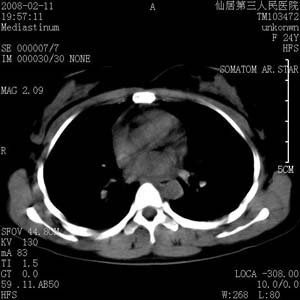

以下是引用zjzjr在2008-2-12 14:32:00的发言:[br]胸腺大点,是不是胸腺瘤或胸腺增生